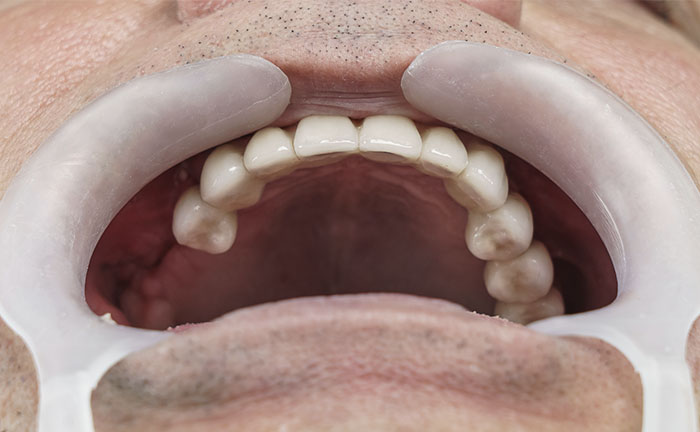

12 resin crowns (fixed teeth)

Another great advantage that derives from the All on 6 method is the immediate load, on the inserted implants your new fixed teeth are fixed in the same session or at most in a second sitting after a few days.

Performed treatments